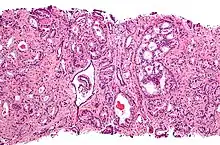

Cribriform pattern: Gleason grade 4

Gleason 4

Gleason pattern 4 glands are no longer single/separated glands like those seen in patterns 1-3. They look fused together, difficult to distinguish, with rare lumen formation vs Gleason 1-3 which usually all have open lumens (spaces) within the glands, or can be cribriform-(resembling the cribriform plate/similar to a sieve: an item with many perforations). Fused glands are chains, nests, or groups of glands that are no longer entirely separated by stroma-(connective tissue that normally separates individual glands in this case). Fused glands contain occasional stroma giving the appearance of "partial" separation of the glands. Due to this partial separation, fused glands sometimes have a scalloped (think looking at a slice of bread with bite taken out of it) appearance at their edges.[4][7]